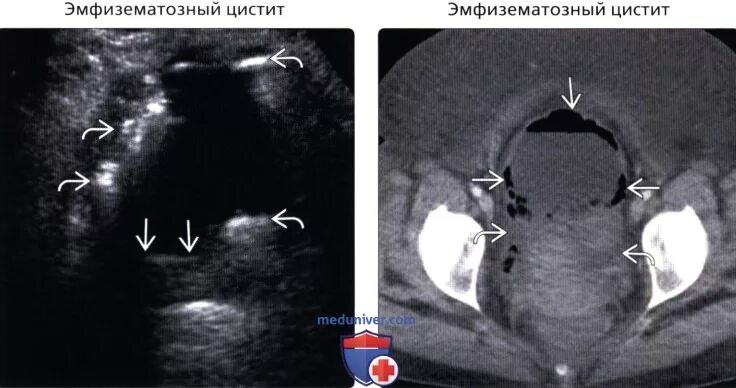

Диффузное утолщение стенок